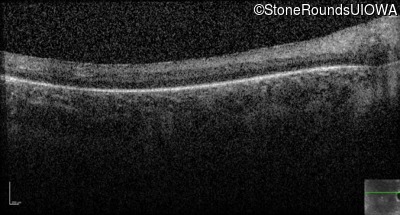

Optical Coherence Tomography - Right - Hand Motion sc

Exemplar / OCT Stack

OCT Stack

Optical Coherence Tomography - Left - Hand Motion sc

Exemplar